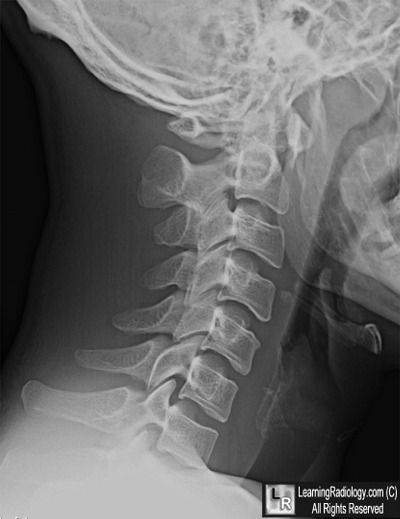

Lateral Radiograph of Cervical Spine

2. Atlanto-axial Subluxation

Atlanto-axial Subluxation

- Distance between the anterior surface of the dens and the posterior surface of the tubercle of C1 is usually 3 mm or less in adults and 5 mm or less in children

- This space is called by many names: predentate space, predental space, atlantodental distance

- The distance may increase slightly on flexion in children but is usually unchanged between flexion and extension in adults

- Forward movement of the atlas on the axis is normally restricted by the transverse ligament